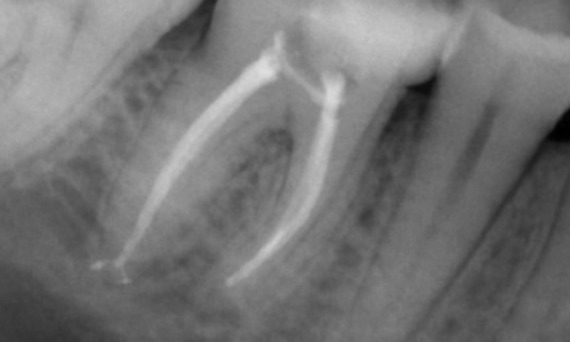

Vorher: Bei der Untersuchung wurde eine Karies-Läsion am unteren rechten ersten Molaren festgestellt. Bei der röntgenologischen Untersuchung zeigte sich die Nähe der Läsion zum Pulpahorn. Zusammen mit den Hauptbeschwerden wurde die endgültige Diagnose einer chronischen irreversiblen Pulpitis gestellt.

Nachher: Die Zugangskavität wurde so konservativ wie möglich gestaltet. Da es sich um einen jungen Patienten handelte, war TruNatomy das System der Wahl. Wir mussten das Dentin so weit wie möglich erhalten, um die Fähigkeit des Zahns zur Bewältigung der okklusalen Belastung und die Langlebigkeit der endgültigen Restauration zu erhöhen.

Kairo, Ägypten